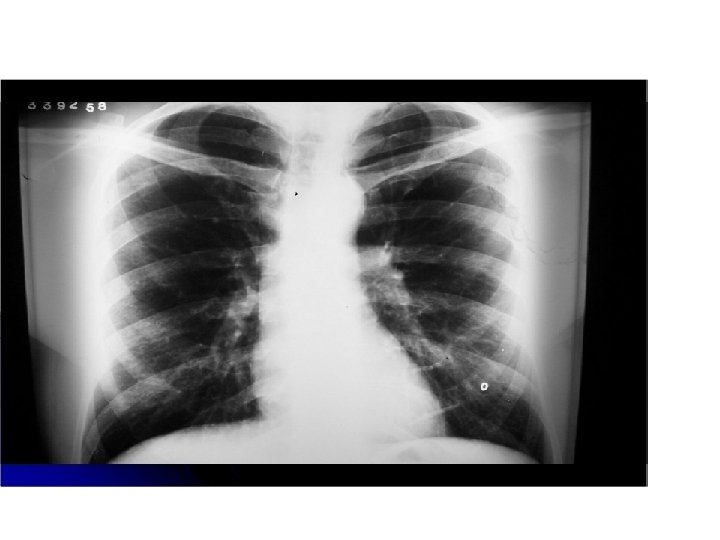

Masa hiliar lobulada con infiltrados interticiales y compromiso del bronquio intermedio. Atelectasia .